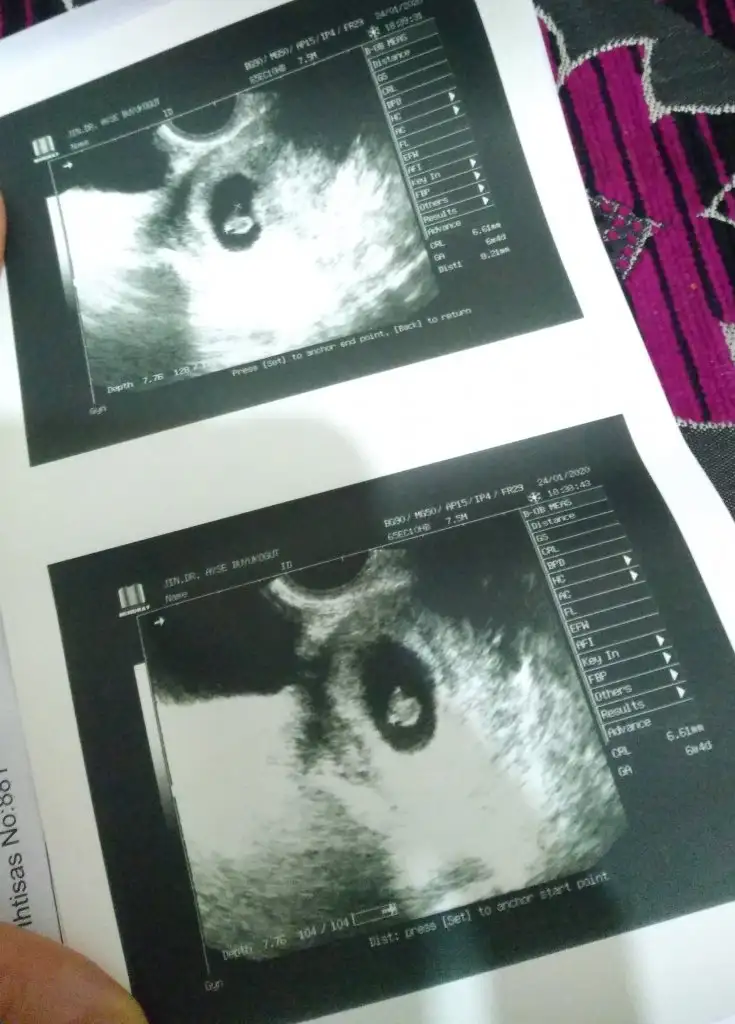

kızlar 6+3 buda benim fasulyem kesenin şekli hakkında yorumlarınızı merak ettiim keseye göre cinsiyet yorumu yapanlardan burdada var mıı😅😅

Ben anlamam ama sanki kese fasulye gibiyse erkek, yuvarlaksa kız gibi geliyor bana. Seninki de erkeğe benziyor 😊